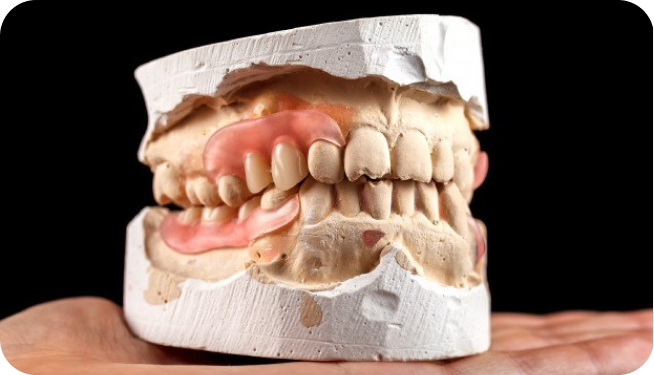

Modelos em Gesso